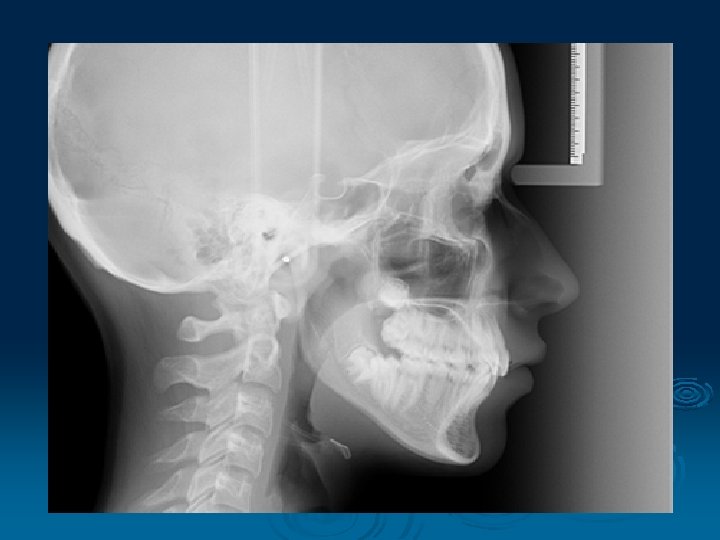

2. Cephalometry § A standardized and reproducible form of skull radiography used extensively in orthodontics to assess the relationships of the teeth to the jaws and the jaws to the rest of the facial skeleton § Main indications - monitoring treatment progress, preoperative evaluation of skeletal and soft tissue patterns, postoperative appraisal of the results of surgery and long-term follow-up studies

§ The pacient is positioned within the cephalostat with the Frankfort plane horizontal, teeth should be in maximum intercuspation § The head is immobilized within the apparatus with the plastic ear rods being inserted into the external auditory meati § The x-ray beam is horizontal and centred on the ear rods § Soft x-rays

Main radiographic projections: lateral PA jaws